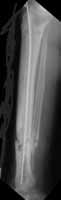

This patient is a 40 year old woman who is five years status post an open tibia fracture. She has healed her tibia, but has developed a chronic osteomyelitis w/ MRSA. She has had several debridements. She's had labeling, with Tetracycline with the debridement ((Dahners JOT)) as well as reaming of her tibia and placement of local antibiotic beads to try and clear the osteomylelitis as well as systemic IV antibiotics. She appeared to heal but recently has had a recurrence with a small pinpoint drainage on the antermedial aspect of her tibia. A CT scan has not been helpful in identifying a nidus of persistent bony infection. She complains of pain that coincides w/ her fluctuating drainage. Any ideas?

Short of segemental resection.....I would again overream, and place antibiotic rod....to fill entire medullary canal dead space.....may not eradicate entirely at this point but will certainly supress.....